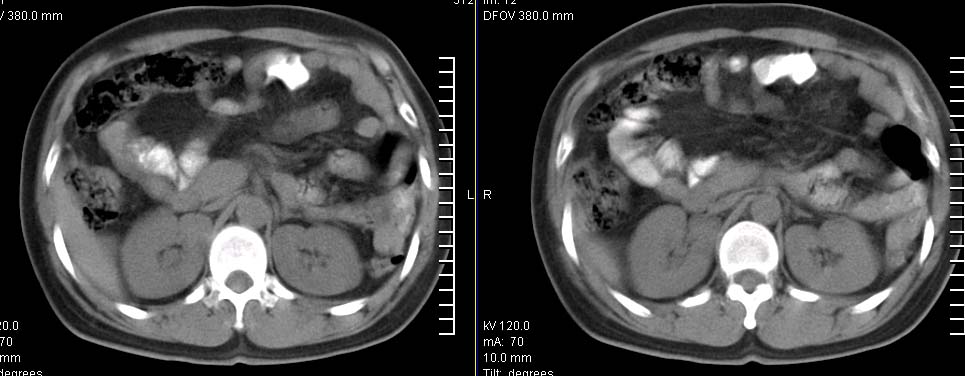

标题: CT9722:卵巢巨大占位,约10*18*21CM大小 [打印本页]

标题: CT9722:卵巢巨大占位,约10*18*21CM大小

卵巢巨大占位,约10*18*21cm大小

卵巢囊腺瘤可能性大.可见低密度

考虑:右侧卵巢囊性瘤可能性大 建议增强扫描。

肿瘤的密度有点高.和子宫差不多?且和子宫相连呢?我考虑来源于子宫,子宫巨大子宫肌瘤可能性大!(局部有坏死?)

囊腺瘤不管是浆液性,还是黏液性的,液体成分应该占的比例很大吧!!这个病灶其实是个实性肿块,更看不到囊腺瘤所能见到的分隔??请笔者提供ct值?望大家再仔细分析??

右侧卵巢的巨大占位,病灶大部分呈实性,以恶性可能大。

右侧附件区巨大囊性肿块,边缘光滑,密度较高,左侧缘由多个低密度区,首先考虑囊腺瘤可能。